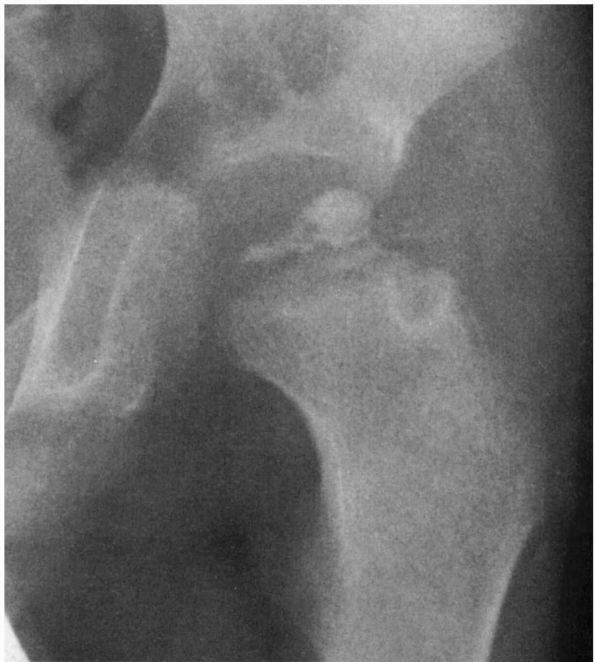

FIGURE 15-19. (A)

Catterall group 4 disease: whole head involvement with either diffuse or central metaphyseal lesions and posterior remodeling of the epiphysis. (B) Catterall group 4 disease 2 to 52 months after onset of symptoms. Note the stage: 14 months—fragmentation; 18 months—early reossification; 25 months—late reossification; 52 months—healed. Note also the growth arrest line and evidence of reactivation of the growth plate along the femoral neck. (Weinstein SL. Legg-Calvé-Perthes disease. In: Morrissy RT, Weinstein SL, eds. Lovell and Winter’s Pediatric Orthopaedics, 5th Ed. Philadelphia: Lippincott Williams & Wilkins, 2001:966-967) |

favorable prognosis than whole femoral head involvement. Catterall

demonstrated the importance of the extent of epiphyseal involvement

relating to prognosis and proposed four groups based on the presence or

absence of seven radiographic signs in 97 untreated hips (Table 15-1; see Figures 15-16 and 15-19).

He reported that 90% of the good results in untreated patients were in